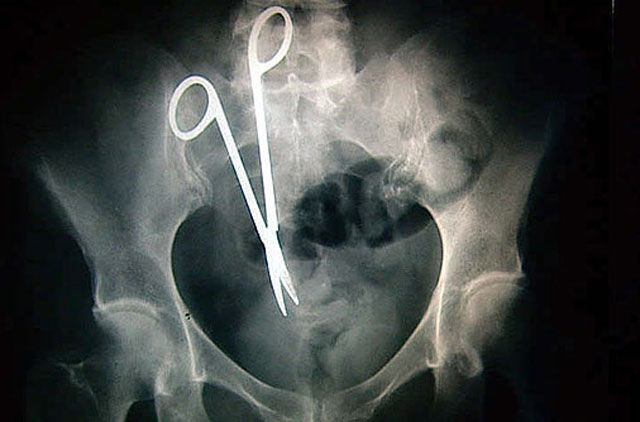

X-ray of scissors left inside Pat Skinner's stomach of Hurstvlle during a operation at St George Hospital, Sydney